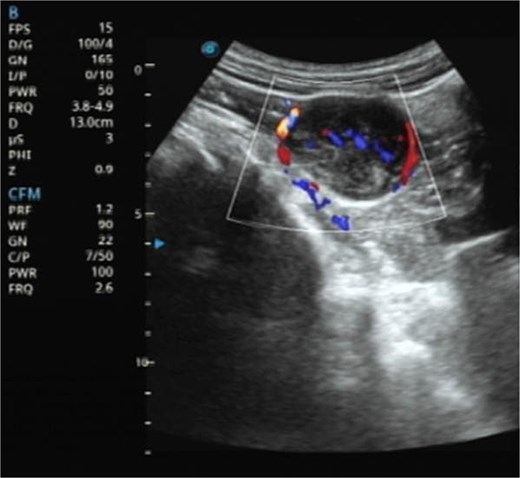

A 61-year-old male presented with dysuria and was subsequently admitted for further management after an incidental 4 cm abdominal mass was detected during routine bladder ultrasonography (Fig. 1). The patient’s vital signs and abdominal examination were unrevealing. Laboratory investigations revealed a full blood count with red blood cell count (RBC) 4.72 × 1012/l, white blood cell count (WBC) 10.56 × 109/l, and platelet count (PLT) 288 × 109/l, indicating no anemia, mild leukocytosis, and a normal platelet count. Renal profile showed serum creatinine 62.9 μmol/l, blood urea nitrogen 3.73 mmol/l, sodium 140.4 mmol/l, chloride 102.2 mmol/l, and bicarbonate 32.3 mmol/l, all within acceptable ranges. Additional laboratory results included C-reactive protein (CRP) 52.46 mg/dl, total bilirubin (TBIL) 30.0 μmol/l, indirect bilirubin (IBIL) 23.4 μmol/l, carcinoembryonic antigen (CEA) 5.16 ng/ml, and carbohydrate antigen 19–9 (CA19–9) 56.26 ng/ml. Serological testing for hepatitis B revealed HBsAg >250 IU/ml (positive), HBsAb 0.317 mIU/ml (negative), HBeAg 0.000 IU/ml (negative), HBeAb >12.000 IU/ml (positive), and HBcAb >40.000 IU/ml (positive), consistent with chronic hepatitis B infection. Tests for hepatitis C antibody and hepatitis A IgM/IgG were negative. No other significant comorbidities or risk factors were identified.

Ultrasonography demonstrates a predominantly hypoechoic mass with peripheral and intralesional blood flow signals.